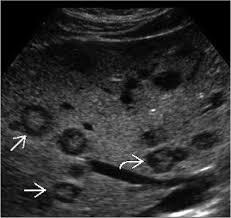

Hydatid sand

Echinococcal cyst

Fine sediment caused by separation of membranes

Can occur in liver or spleen

Water lily sign

Undulating membrane